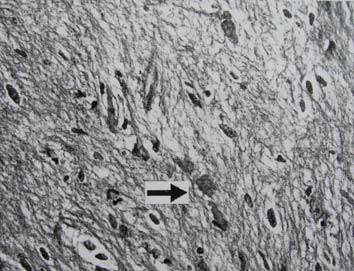

33.Seorang laki-laki gemuk usia 28 tahun dibawa dengan riwayat sakit kepala dan diplopia selama dua bulan terakhir. Ternyata pasien mengalami lesi sebagaimana yang ditunjukkan pada fotomikrograf di bawah in. Apakah yang dijelaskan oleh tanda panah pada fotomikrograf tersebut?

A. Telangiestasia kapilaris

B. Gemitosit

C. Serat Rosenthal

D. Pembuluh darah normal

E. Granula melanin